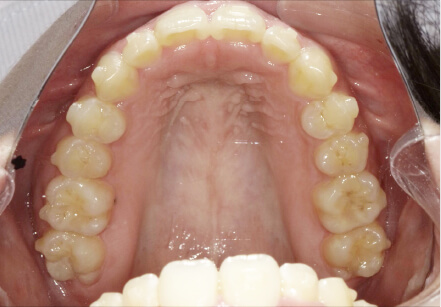

叢生の症例

28歳

女性

カウンセリング・診断結果

IPR承諾、アレルギー無

全顎アライナー矯正

クリアライナー使用

痛み・歯根吸収・歯肉退縮・虫歯・後戻り

990,000円、3年